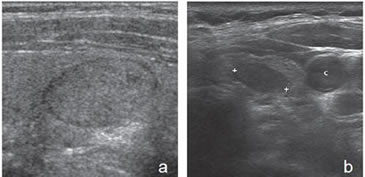

Son tumores sólidos, únicos, iso o hiperecogénicos, muy homogéneos, encapsulados, de contornos lisos, de forma ovoidea, sin microcalcificaciones (Figura 3b). En el 80% de los casos se puede observar un halo hipoecogénico. Ocasionalmente pueden ser discretamente hipoecogénicos. La vascularización habitualmente esta aumentada en la periferia con vasos que se descuelgan hacia el centro de la lesión (Figura 12). A diferencia de los nódulos coloideos generalmente no se observan imágenes quísticas (Figura 32).

En este grupo se encuentran principalmente las neoplasias foliculares benignas (adenomas) o malignas (carcinomas). Están compuestos de células foliculares o células de Hurthle en distinta proporción, y son encapsuladas. La mayoría (85%) corresponden a adenomas foliculares. Sin embargo, con el mismo patrón se puede presentar el carcinoma folicular bien diferenciado, aunque este suele ser de mayor tamaño, hipoecogénico, de contenido más heterogéneo, la capsula de mayor espesor (Figura 33a y b) y el aumento de la vascularización es difuso22. La presencia de calcificaciones intranodulares conlleva mayor riesgo de malignidad.

En la práctica, todos los nódulos con patrón neoplásico van a ir necesariamente a PAAF para poder determinar su etiología. De estos, al menos 50% van a ser benignos y entre 5%-15% van a ser carcinomas foliculares. Dentro de este grupo, un porcentaje menor va a corresponder a cáncer papilar variedad folicular21.